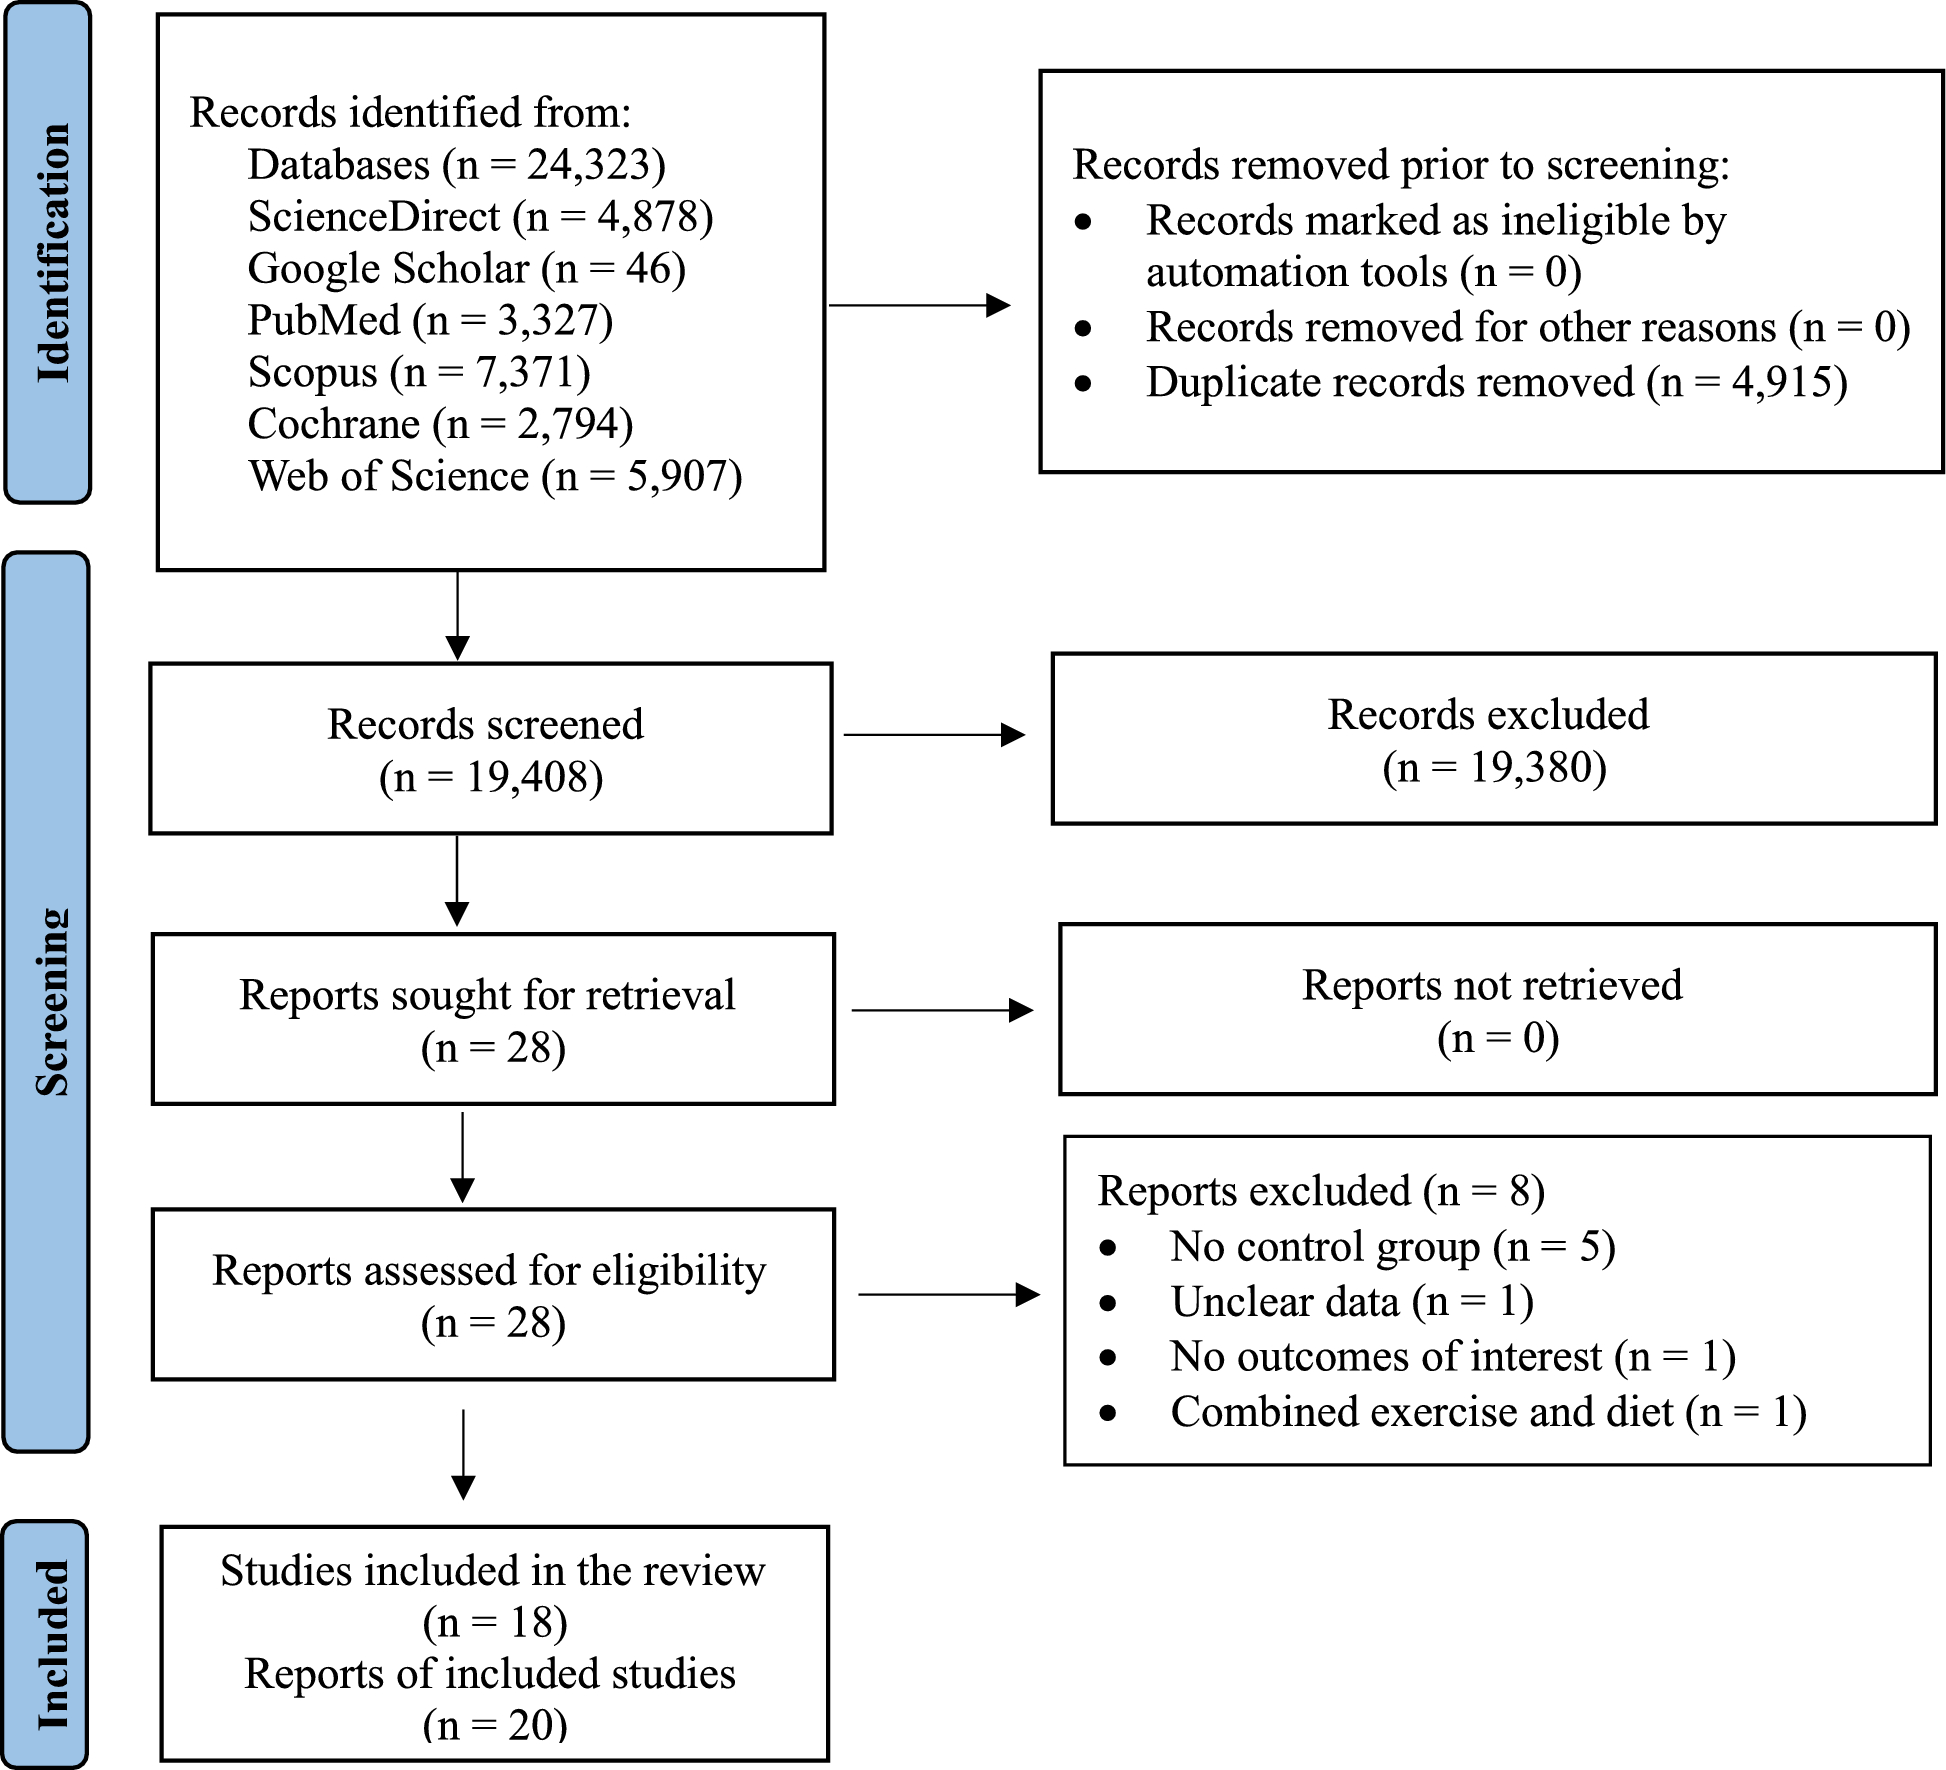

Bhupathiraju SN, Hu FB. Epidemiology of obesity and diabetes and their cardiovascular complications. Circ Res. 2016;118(11):1723–35. https://doi.org/10.1161/CIRCRESAHA.115.306825.